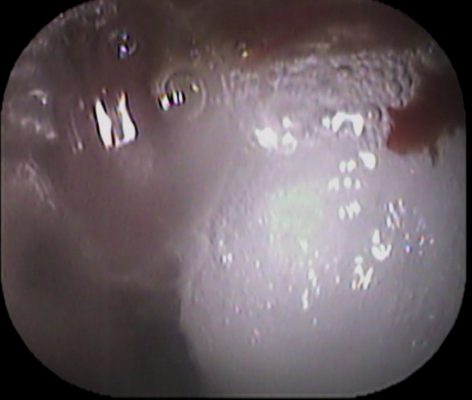

軟らかい組織で綿棒で擦ると 白い膿が出て出血しました↓

最終的にかなりの出血量に![]()

続いては口からもおこないます↓

(口から綿棒挿入中の写真です↓)